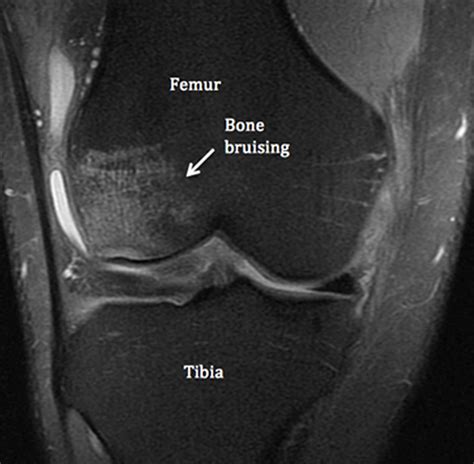

Diagnosing a bone contusion knee involves a combination of physical examination and imaging tests. The diagnostic process typically includes:

• Imaging Tests: X-rays, MRI, or CT scans may be used to visualize the bone and surrounding tissues. MRI is particularly useful for detecting bone contusions.